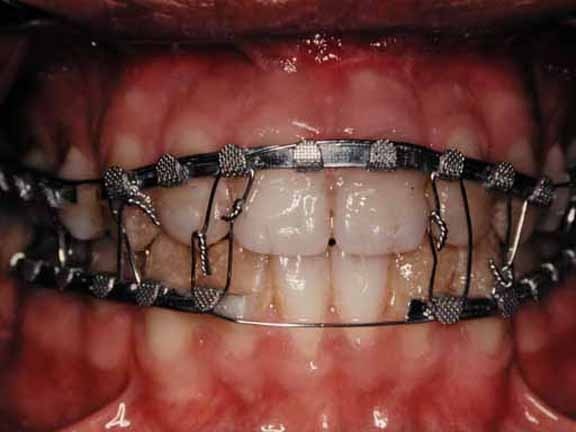

1. Intermaxillary Fixation (IMF)

We perform IMF for selected jaw and dental injuries that require stabilization but not hospital admission.

This involves temporarily fixing the upper and lower jaws to restore alignment and allow proper bone healing.

We use eyelet wiring, Erich’s arch bars, or elastic fixation systems, all under sterile conditions and local anesthesia, with regular follow-up.